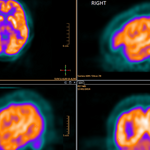

FDG PET-CT In Clinical Decision-Making

Researchers have published the results of the largest prospective multicenter trial conducted of FDG-PET/CT in head and neck cancer, providing data on clinical decision-making. The non-randomized phase two trial, ACRIN 6685, followed 287 patients with newly diagnosed stage T2 to T4 disease, all being considered for surgery when at least one side of the neck had no evidence of lymph node involvement based on a physical exam, preoperative MRI and/or a CT evaluation (clinically node-negative or cN0). It found that FDG-PET/CT imaging achieved a true negative in 94 percent of patients (by…